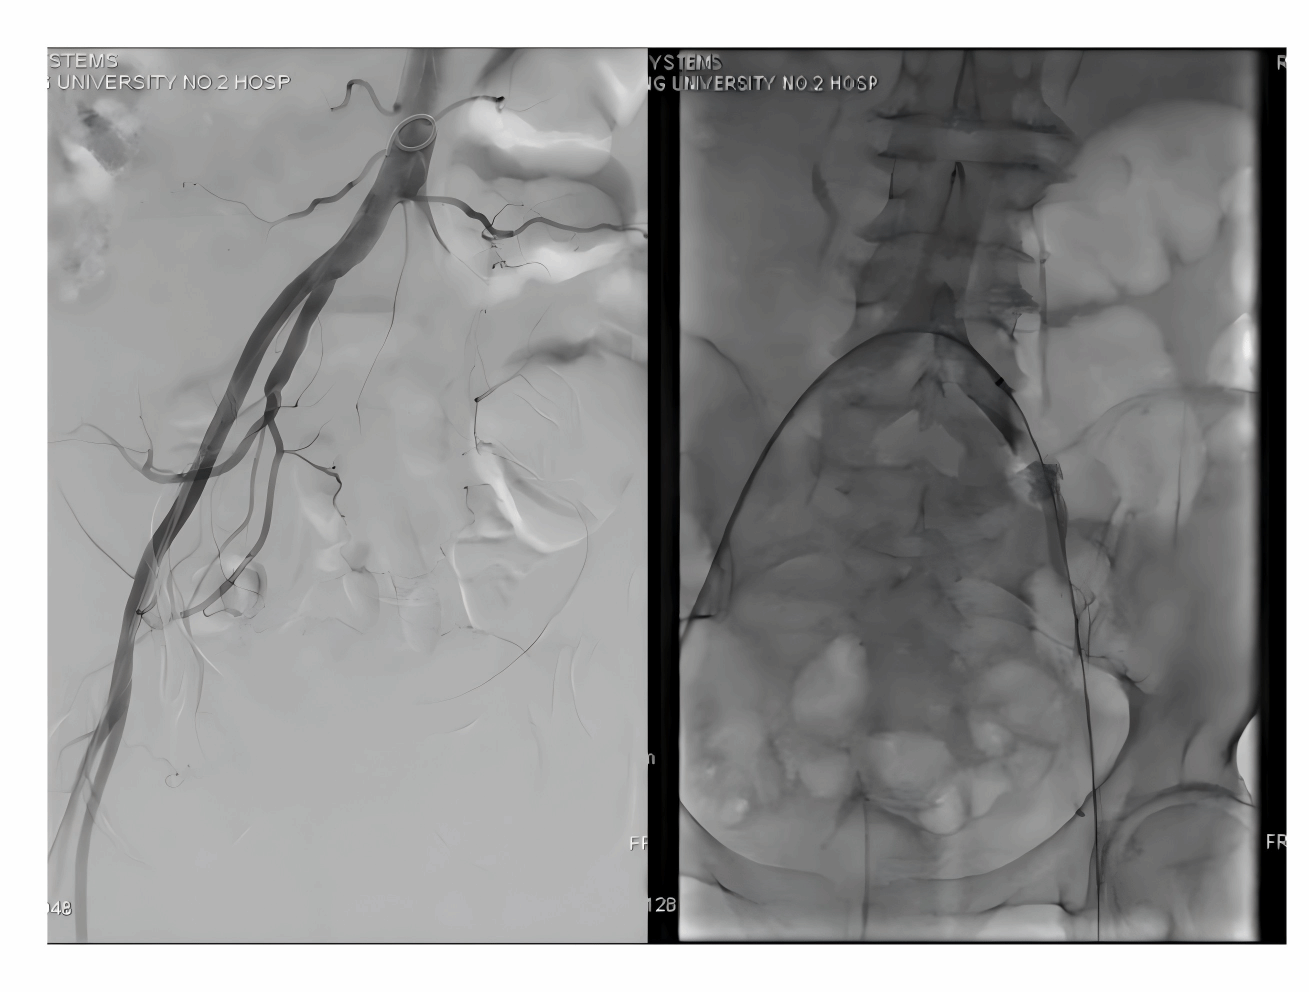

患者术前造影患侧肢体血管完全不显影

开通后的患侧动脉造影